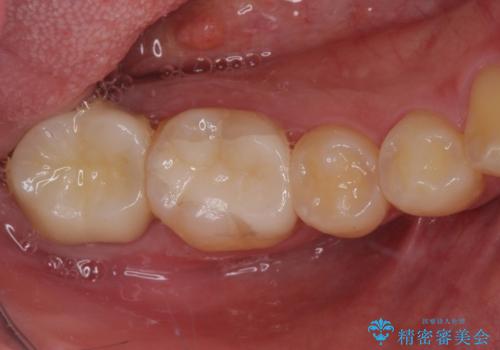

銀歯を白くしたい セラミックによる審美歯科治療

途中来院されない時期があったため、初診から終了まで期間がかかりましたが、根管治療を行った歯の根尖病変はいずれも改善を確認することができました。

口腔内の金属が全てなくなり、患者様には大変満足していただきました。